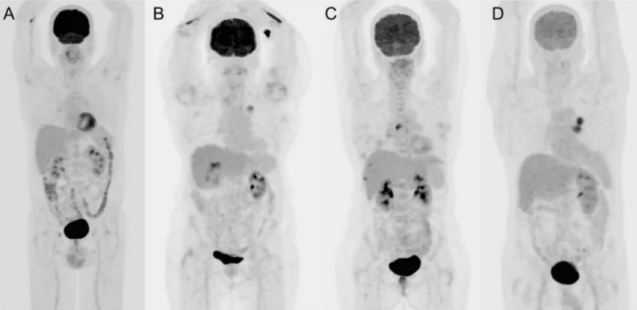

Breakdown what PET/CT is a combination of (what each part specifically scans)

PET – scans the patient’s physiology

CT – scans the patient’s anatomy

What type of process is commonly seen in cancer?

Metabolic process – hypermetabolic

Why do we like to use FDG as a pharmaceutical in PET?

It’s a sugar that is very similar to glucose

As cancer uses metabolic processes, it uses glucose as its main form of energy – we take advantage of this by binding the radioactive material with a pharmaceutical that’s similar in structure to glucose so that we can visualize where the cancer is based on its metabolism

What happens to the FDG when it’s up-taken by the cancer cells?

Instead of breaking down FDG and using it as energy, it will just accumulate in the cancer cell – makes the cancer more visible on our PET images

When would we perform a whole body acquisition?

If the patient has melanoma – want to image cancer from head-to-toe